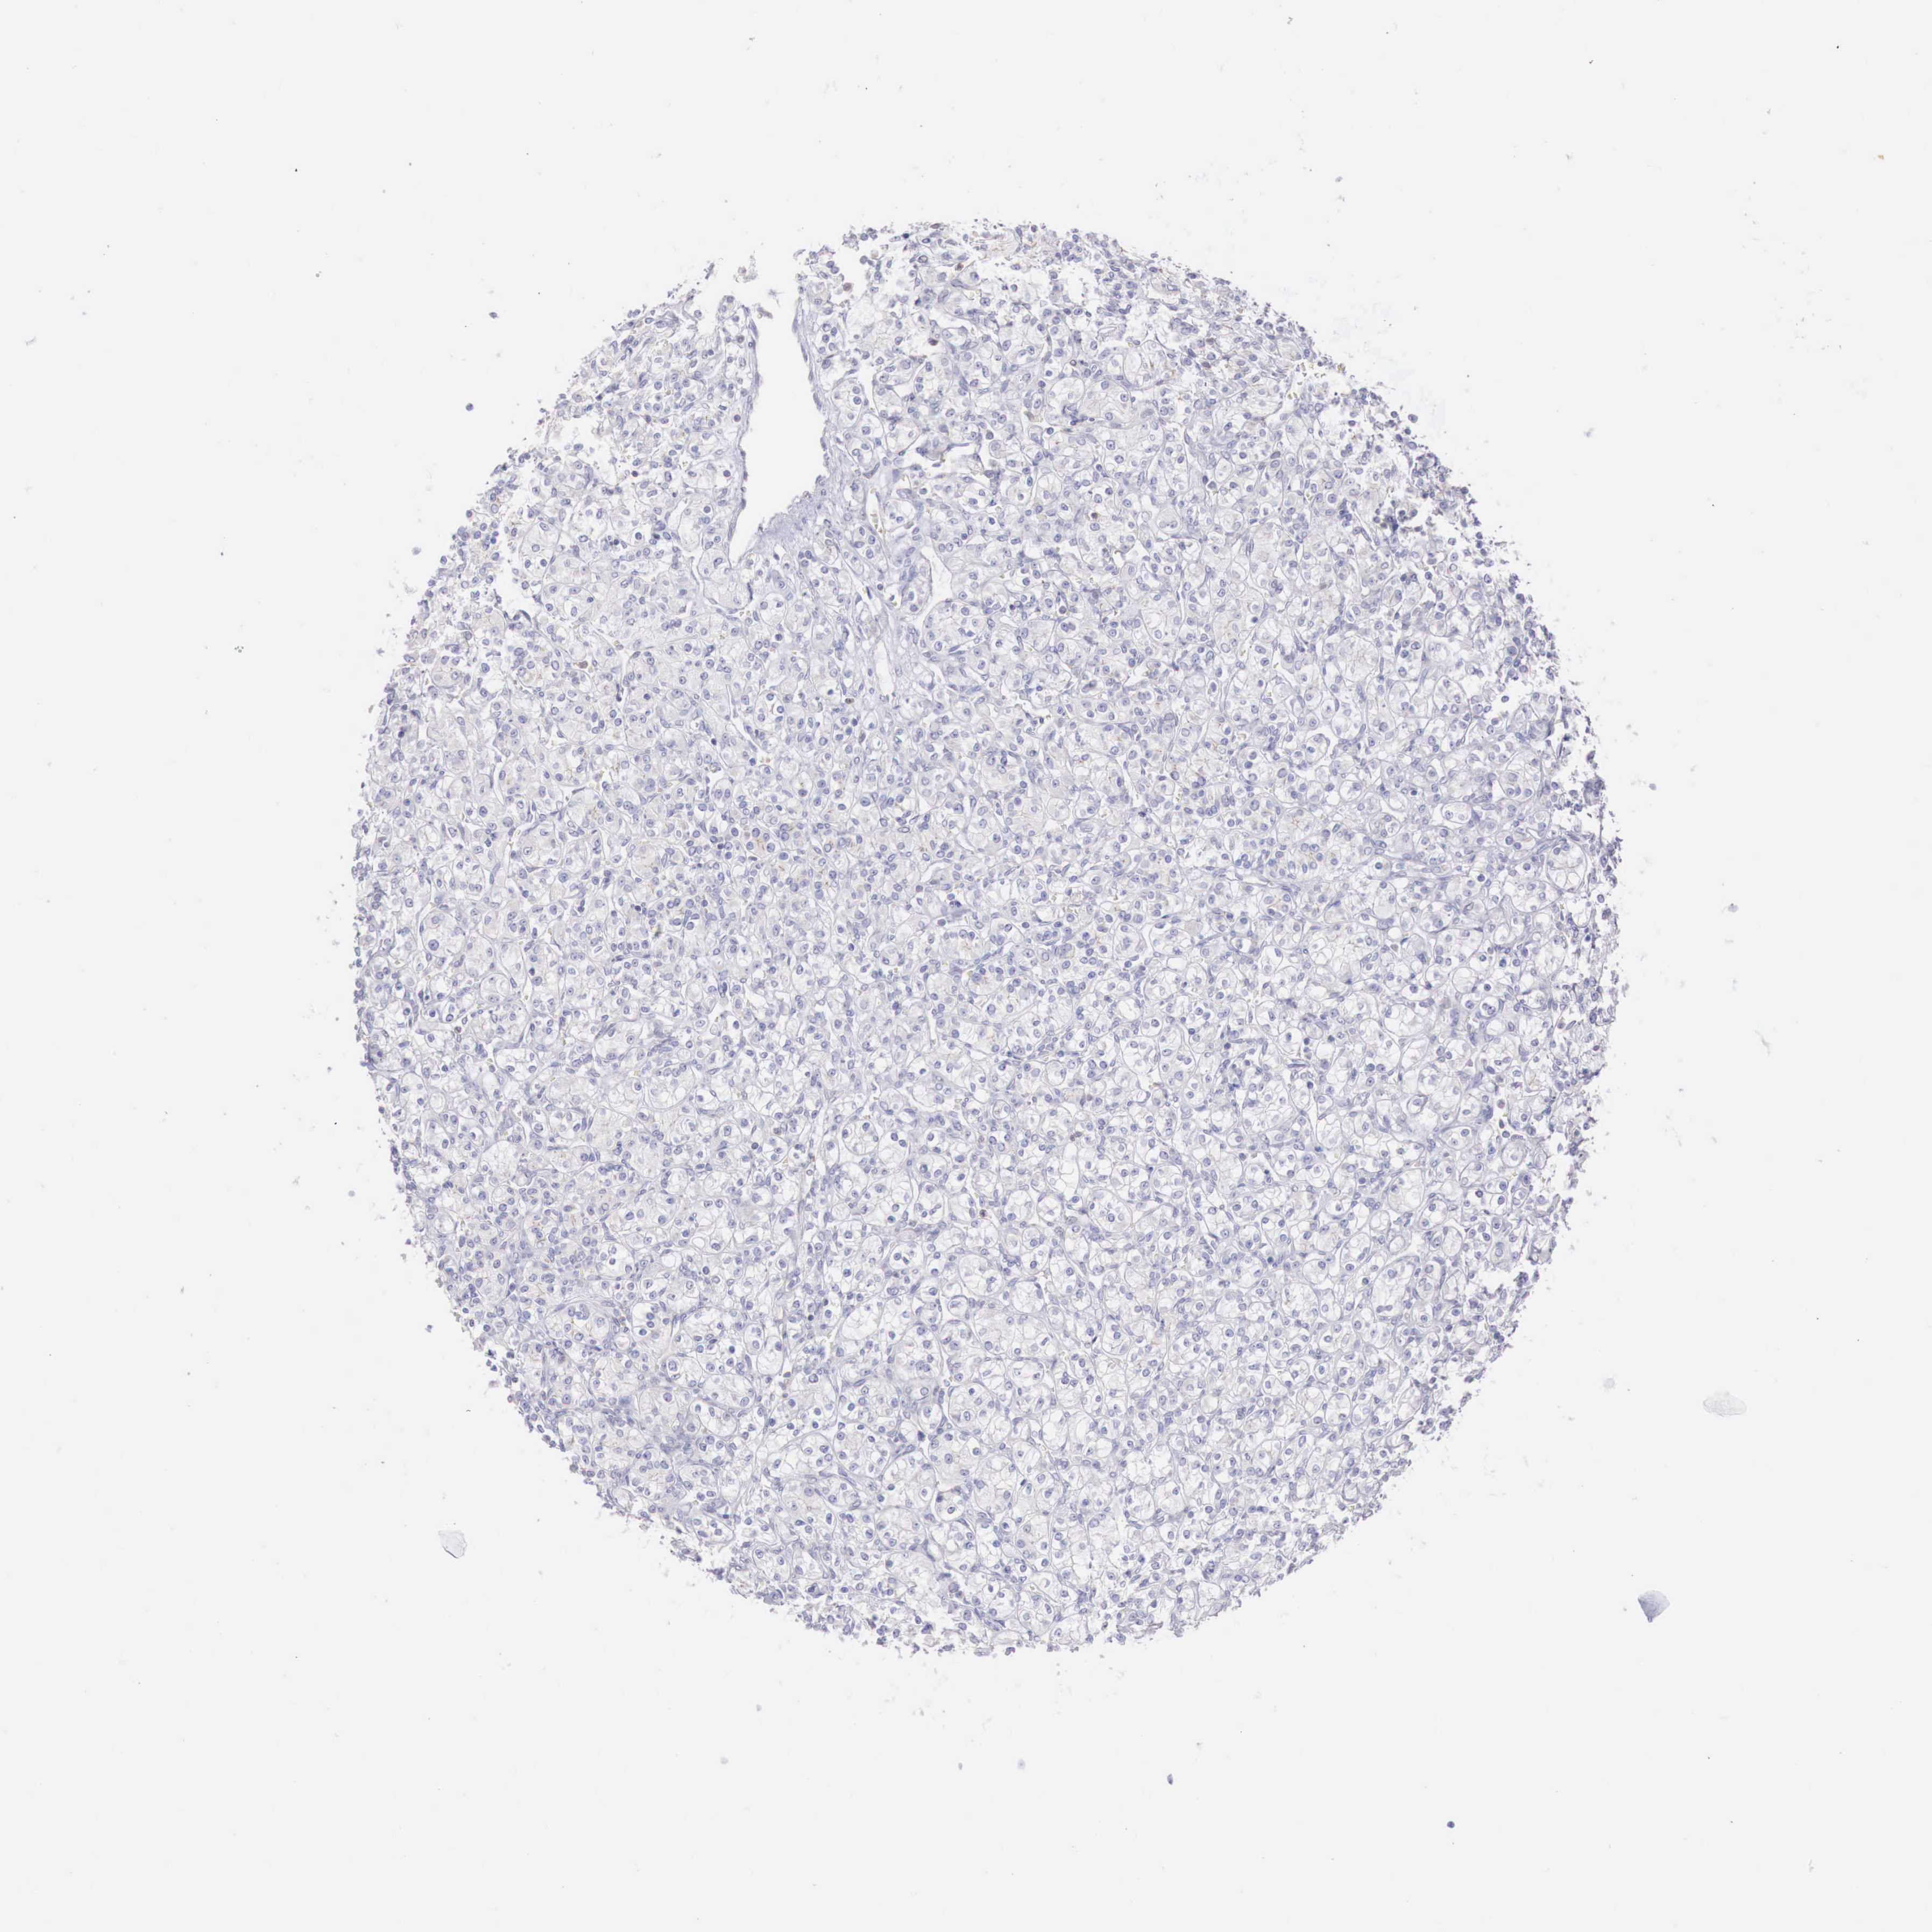

CANCER RENAL CANCER Show tissue menu

KIDNEY CHROMOPHOBE (TCGA) - Interactive survival scatter ploti

The Survival Scatter plot shows the clinical status (i.e. dead or alive) for all individuals in the patient cohort, based on the same data that underlies the corresponding Kaplan-Meier plots. Patients that are alive at last time for follow-up are shown in blue and patients who have died during the study are shown in red.

The x-axis shows the expression levels (FPKM) of the investigated gene in the tumor tissue at the time of diagnosis. The y-axis shows the follow-up time after diagnosis (years). Both axes are complimented with kernel density curves demonstrating the data density over the axes. The top density plot shows the expression levels (FPKM) distribution among dead (red) and alive patients (blue). The right density plot shows the data density of the survived years of dead patients with high and low expression levels respectively, stratified using the cutoff indicated by the vertical dashed line through the Survival Scatter plot. This cutoff is automatically defined based on the FPKM cutoff that minimizes the p-score. The cutoff can be changed by dragging the vertical line or by entering a cutoff value in the square labeled "Current cut-off".

Under the Survival Scatter plot the p-score landscape (black curve; left axis) is shown together with dead median separation (red curve; right axis). Dead median separation is the difference in median mRNA expression between patients who have died with high and low expression, respectively. It is calculated as follows: median FPKM expression of dead patients with high expression - median FPKM expression of dead patients with low expression. This is intended to aid the user in visually exploring custom cutoffs and the associated p-scores and dead median separation.

Individual patient data is displayed and can be filtered by clicking on one or more of the category buttons on the top of the page. Categories describing expression level and patient information include: high, low, alive, dead, female, male and tumor stages. The scale of the x-axis can be toggled between linear and log-scale by clicking on the "x log" button. Mouse-over function shows TCGA ID, patient information and mRNA expression (FPKM) for each patient.

& Survival analysisi

Kaplan-Meier plots summarize results from analysis of correlation between mRNA expression level and patient survival. Patients were divided based on level of expression into one of the two groups "low" (under cut off) or "high" (over cut off). X-axis shows time for survival (years) and y-axis shows the probability of survival, where 1.0 corresponds to 100 percent.

TRIM13 is not prognostic in Kidney Chromophobe (TCGA)

Best expression cut offi

Based on the FPKM value of each gene, patients were classified into two groups and association between prognosis (survival) and gene expression (FPKM) was examined. The best expression cut-off refers the FPKM value that yields maximal difference with regard to survival between the two groups at the lowest log-rank P-value. Best expression cut-off was selected based on survival analysis .

When clicking on this number, the vertical dashed line indicating cut-off, the interactive survival plot, and the Kaplan-Meier curve will be adjusted to show results based on the best expression cut-off.

: 10.11

Average pTPM 8.5

Number of samples 64